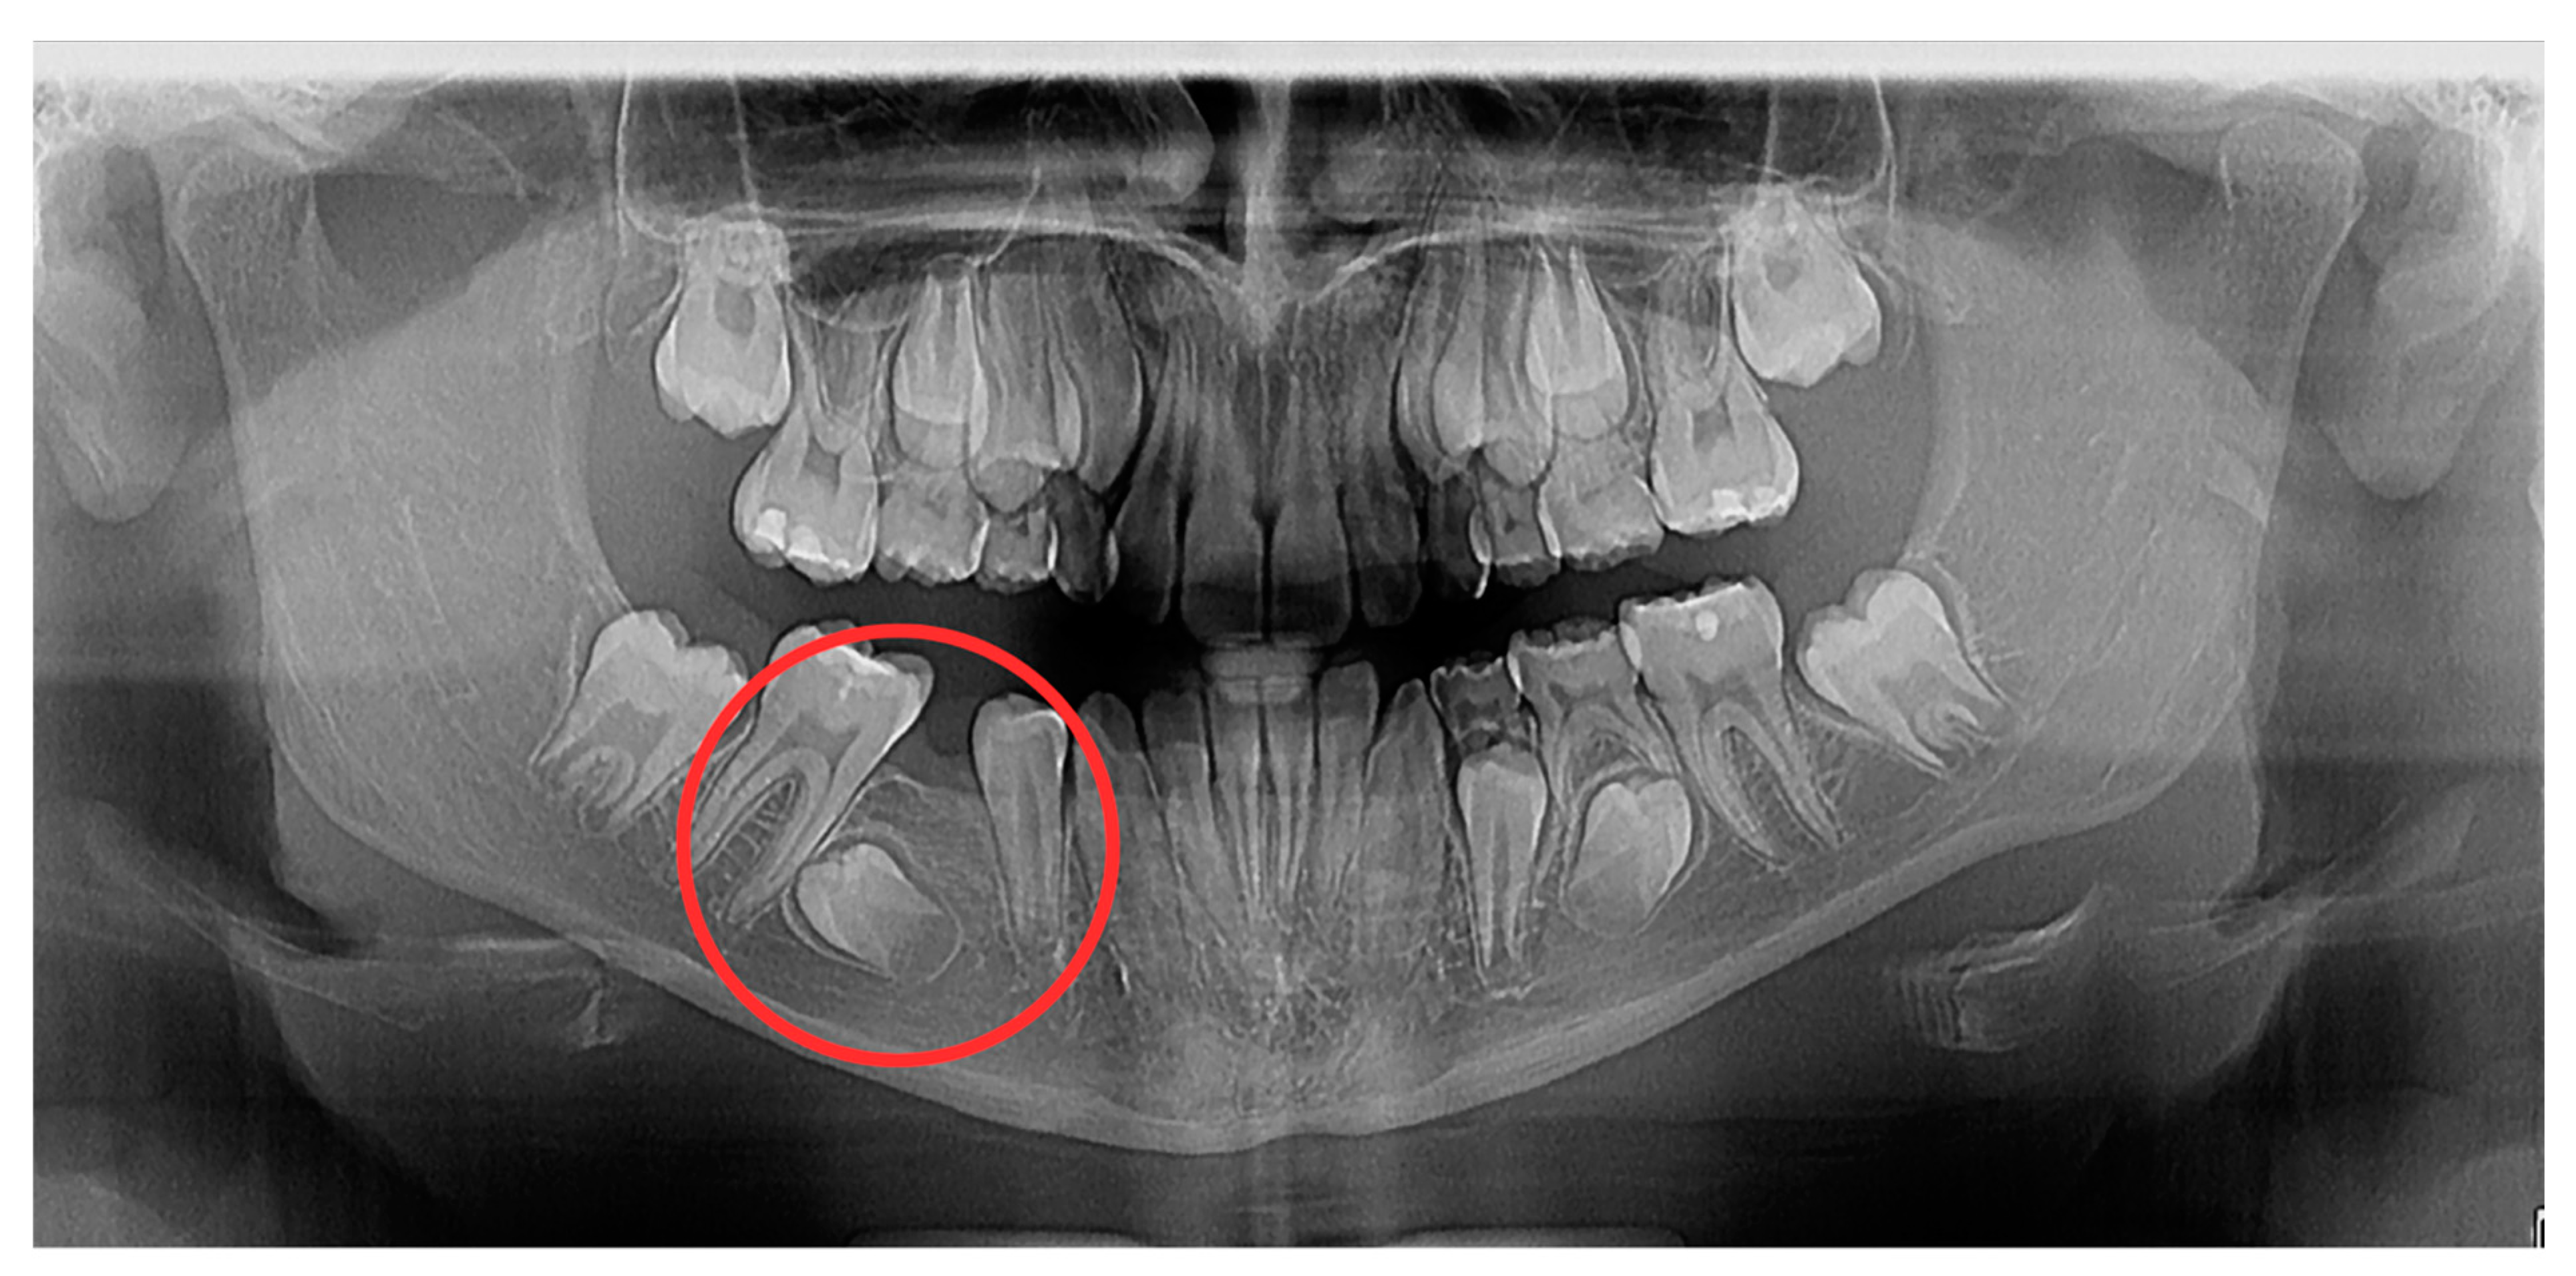

2. Case Report

2.1. Examination, Diagnostics, and Initial Therapeutic Management